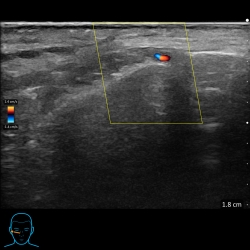

16/09/21My Clarius ultrasound to the rescue again!This dip in the forehead was bothering my patient.Hey presto, my trusted ultrasound scan helped me diagnose a frontal vein as the cause. I could then choose a...

Read moreUltrasound use prior to injecting fillers in aesthetics

02/09/21Since March 2021 I have been using my aesthetic ultrasound scan to improve my patient’s safety when injecting fillers. The ultrasound company tells me I was one of the first in the UK to use...